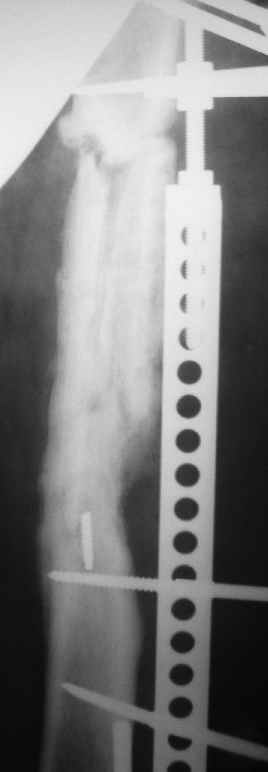

Больной 40лет, поступил 08.06.05г. с закр. оскольчатым переломом бедренной кости в с/3 и в/3 со смещ., 10.06.05г. выполнен остеосинтез LCP

,ч/з 3нед. после операции вскрыта нагноившаяся гематома, промывная система 1нед., через 3-и месяца пластина удалена в связи с инфекцией, секвестрэктомия, ЧКДО. АВФ 8мес.,периодически абсцедирование мягких тканей, санирующие операции, в настоящее время вскрыт абсцесс в с/3 бедра, м/ткани в обл. стержней инфицированы, полость абсцесса сообщается с проксим. и частью дист. стержнейдальнейшая тактика?

6. Свежие рентгенснимки без конструкции.